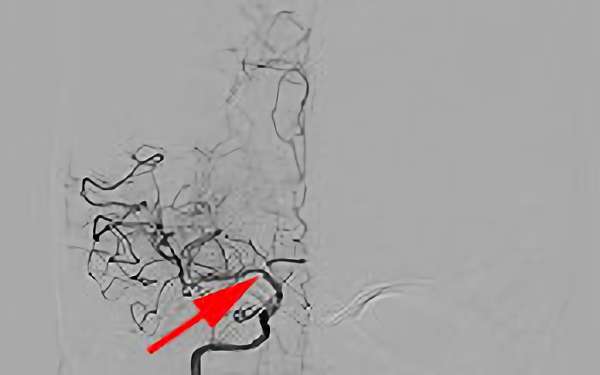

452

'19年4月6日

アテローム血栓性 脳梗塞

60代

大阪府の病院